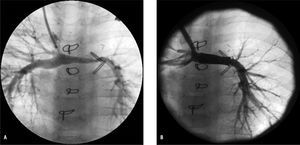

De los 4 pacientes operados con la técnica de Sano, 3 precisaron angioplastia de arterias pulmonares, que se realizó en 2 casos con catéter balón (debido al escaso peso de los pacientes y el pequeño tamaño de sus arterias pulmonares) a través del conducto o del Glenn, y en otro paciente al que se había realizado doble Glenn por persistencia de vena cava superior izquierda, se implantó stent CP de Numed de 22 mm de longitud sobre «balón en balón» de 8 mm en el segmento de las arterias pulmonares comprendido entre las dos cavas, que había ido quedando progresivamente hipoplásico (fig. 3). Los detalles angiohemodinámicos y de la técnica empleada en las angioplastias de arterias pulmonares se exponen en la tabla 2.

Fig. 3. A: angiografía en vena cava superior en paciente con Norwood Sano y Glenn, con doble vena cava superior, que desarrolla hipoplasia de arteria pulmonar izquierda (calibre mínimo de 2,2 mm). B: angiografía postangioplastia con stent CP de Numed de 22 mm de longitud implantado sobre balón en balón de 8 mm; la arteria pulmonar izquierda presenta ahora calibre mínimo de 6,4 mm.

En cuanto a la afección de las arterias pulmonares, la técnica modificada de Sano (shunt desde el ventrículo derecho) evitó en nuestros pacientes el problema de la desconexión o hipodesarrollo de la arteria pulmonar izquierda, pero no evitó las estenosis de arterias pulmonares en la zona de inserción del conducto22. La incidencia de estenosis significativa de ramas pulmonares tras la cirugía Norwood (antes del Glenn o Fontan o incluso después de éste) referida en la literatura oscila entre el 40 y el 62%23,24. En nuestra serie observamos especial tendencia a presentar estenosis severas y/o hipodesarrollo en la zona de confluencia entre ambas arterias pulmonares, donde pueden quedar restos de tejido ductal, y que resulta más difícilmente accesible al cirujano por quedar posterior a la neoaorta ascendente, habitualmente dilatada. Otro factor posiblemente implicado en el hipodesarrollo de esta zona es la presencia de doble cava superior, pues tras el Glenn el flujo de cada vena cava superior se dirige a la arteria pulmonar ipsolateral; 2 de los 3 pacientes que precisaron stent en esa zona presentaban doble cava superior. Otra de las peculiaridades de las angioplastias de arterias pulmonares realizadas en pacientes tras los estadios I o II es que presentan elevada incidencia de reestenosis (posiblemente por persistencia de tejido ductal), pero también suele tratarse de pacientes de bajo peso y pequeño tamaño de las arterias pulmonares que no permiten en algunos casos la implantación de stents redilatables. Para el seguimiento de estas estenosis tras la angioplastia, es fundamental la utilización de la RM o angiografía por TC. La implantación de stents de menor tamaño (coronarios o periféricos) y que precisan introductores de menor tamaño podría ser una opción, pero limitan el desarrollo de la arteria y con el crecimiento somático del paciente acaban creando una estenosis. En nuestros pacientes, intentamos utilizar la angioplastia con balón en los pacientes más pequeños (aunque precisaran redilatación por reestenosis a corto o medio plazo), y retrasar la implantación del stent para emplear stents redilatables (Palmaz, Ev3 o CP de Numed) a través de vainas de 10-11 Fr, que se introdujeron sin complicaciones por la vena yugular en niños de hasta 10 kg de peso. Quizá en el futuro el empleo de nuevos stents pediátricos, como los reabsorbibles25 (Biotronik) o redilatables de bajo perfil (growth stent)26, aún en fase de ensayo clínico, podrían facilitar y mejorar el tratamiento de estas lesiones. Por otra parte, la implantación de stents en la zona de la confluencia de las arterias pulmonares puede condicionar la técnica quirúrgica empleada en el estadio III: en 2 de nuestros pacientes con el stent en esta posición el conducto extracardiaco desde vena cava inferior tuvo que ser anastomosado a la arteria pulmonar derecha, frente a la conexión del Glenn (fig. 2B), y el postoperatorio transcurrió sin complicaciones.